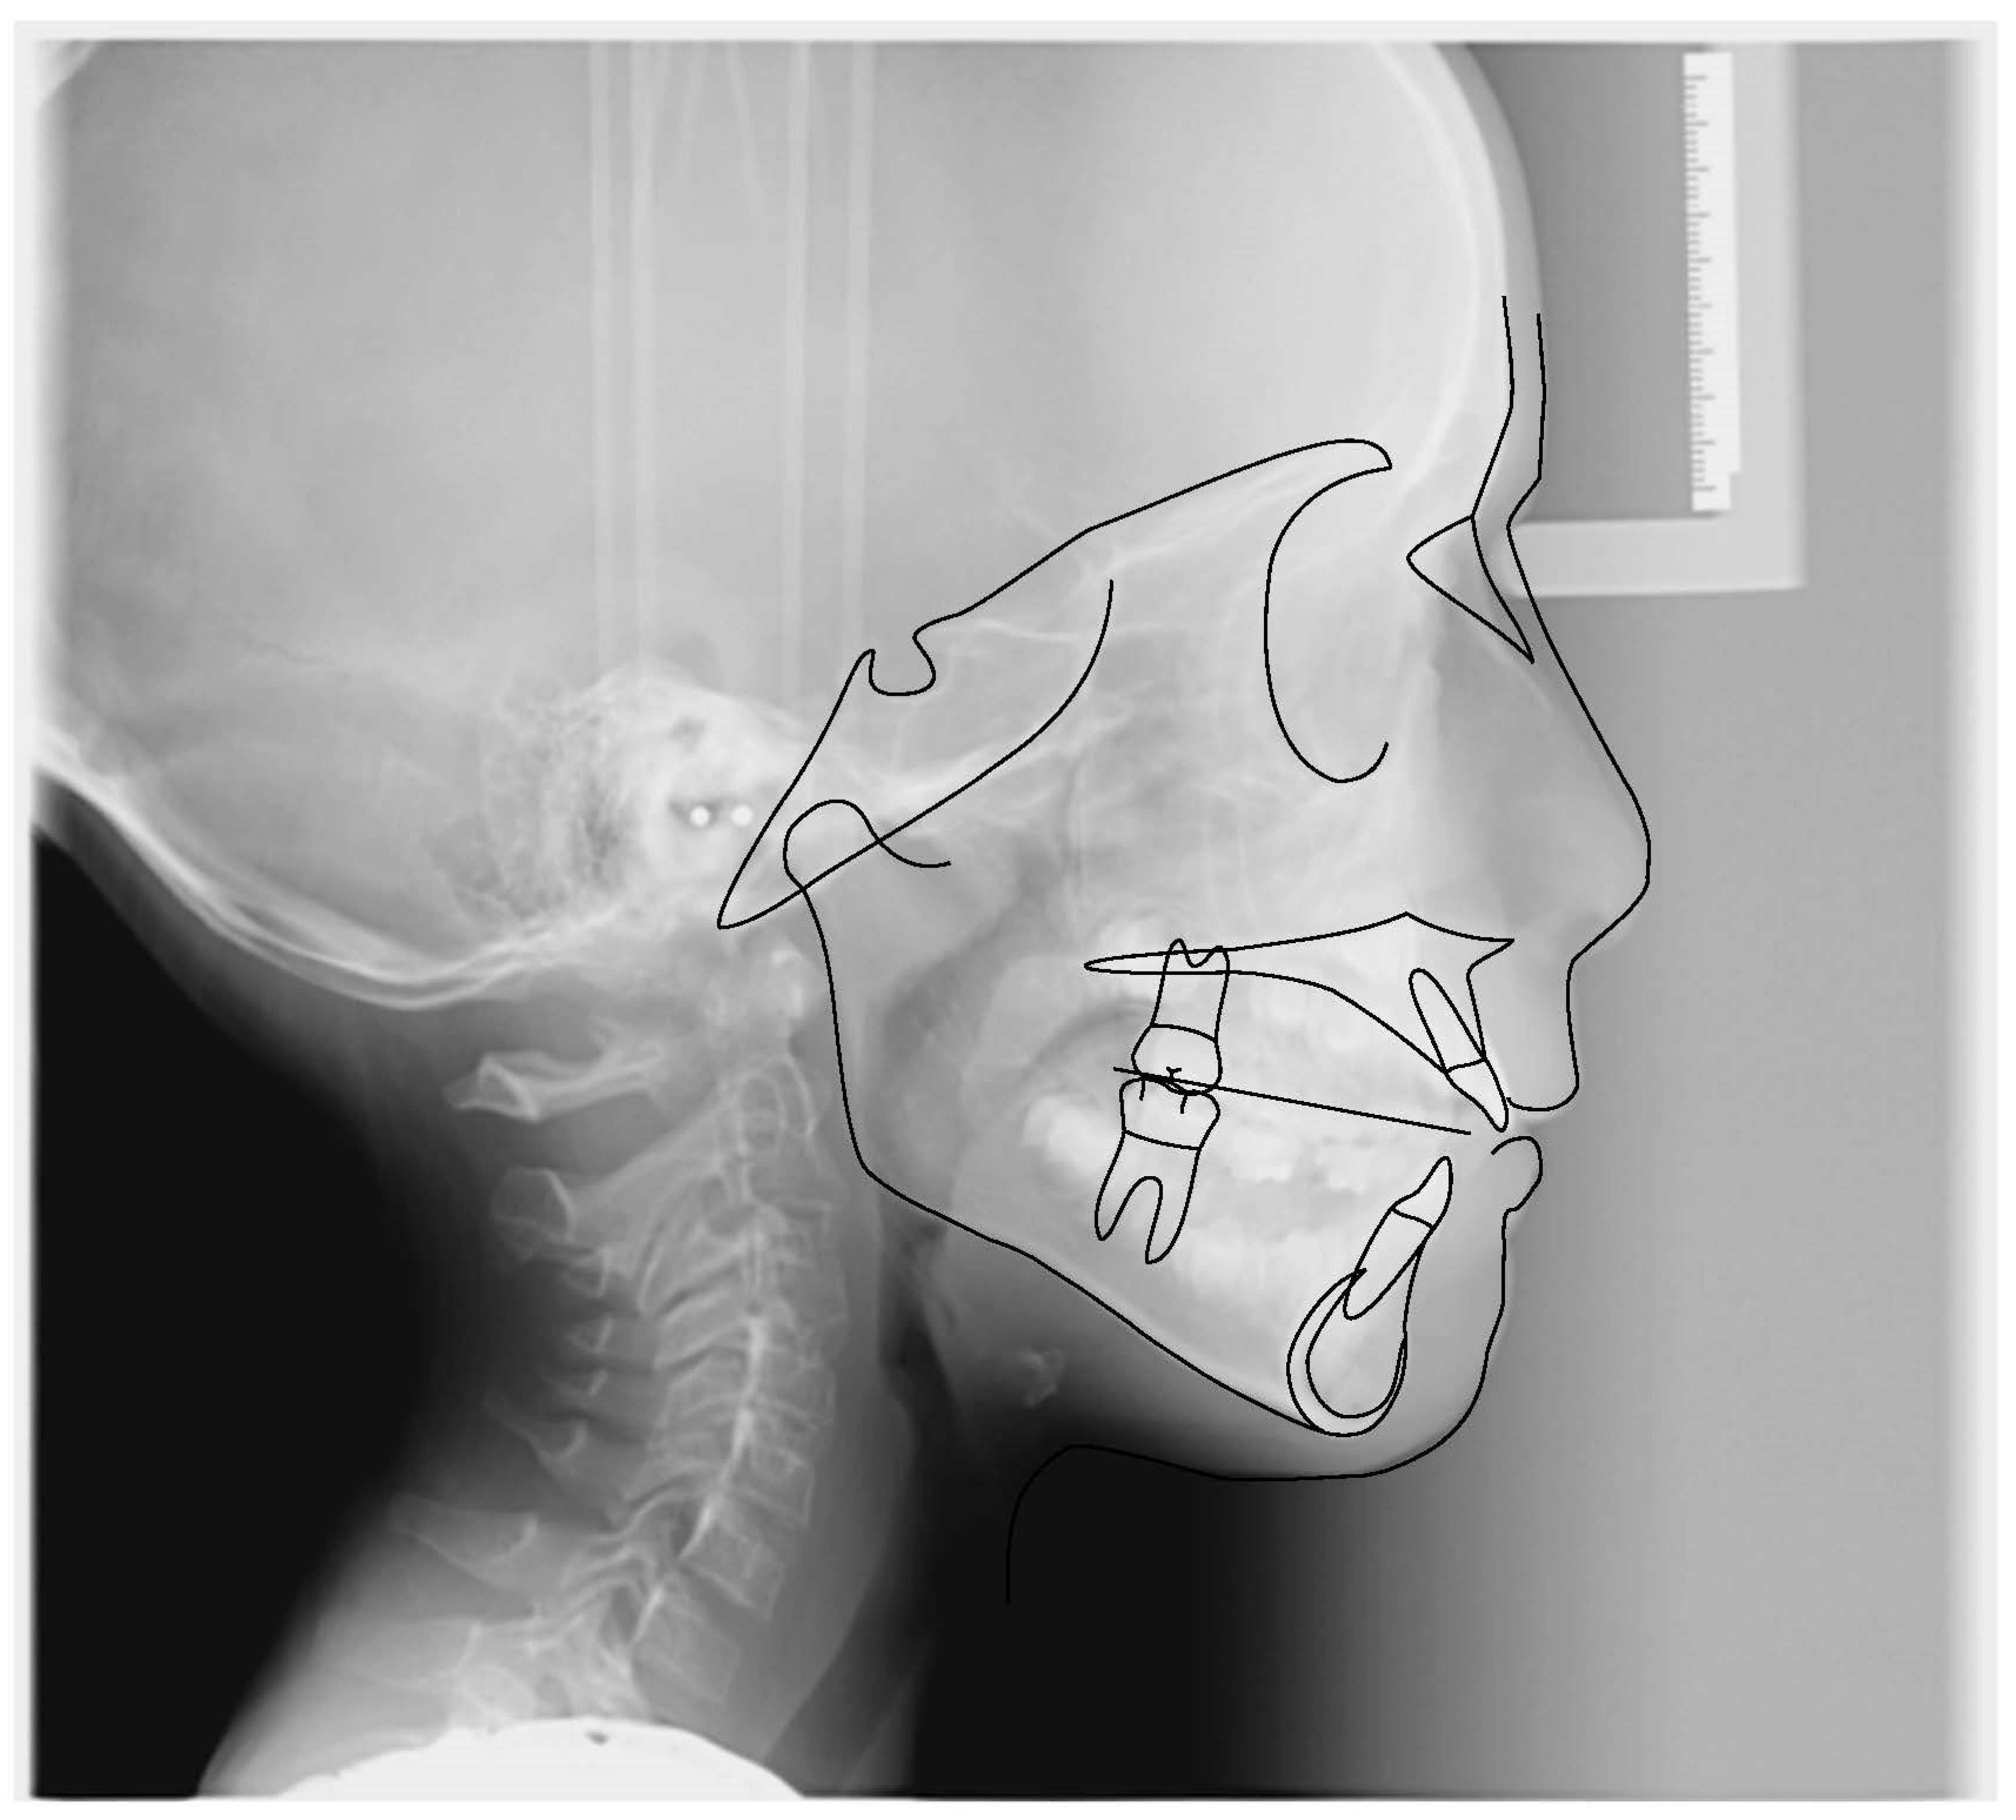

3.1. Clinical Case #1

| Cephalometric Analysis after Treatment | Val | Dev | Min | Med | Max | Diff |

|---|---|---|---|---|---|---|

| SNA | 76.6° | −xx | 80° | 82° | 84° | 3.4° |

| SNB | 74.1° | −xx | 78° | 80° | 82° | 3.9° |

| ANB | 2.5° | N | 0° | 2° | 4° | 0° |

| sna-snp^Go-Gn | 23.3° | N | 15° | 20° | 25° | 0° |

| S-N^sna-snp | 12.7° | N | 7° | 10° | 13° | 0° |

| S-N^PO | 25.7° | xxx | 11° | 14° | 17° | 8.7° |

| S-N^Go-Gn | 36.1° | N | 27° | 32° | 37° | 0° |

| SNBa | 138.2° | x | 124° | 129° | 134° | 4.2° |

| SND | 71.2° | −xx | 74° | 76° | 78° | 2.8° |

| IS^II | 130.3° | N | 125° | 130° | 135° | 0° |

| IS:N-A | 1.6 | −xx | 3 | 4 | 5 | 1.4 |

| II:N-B | 2.3 | −x | 3 | 4 | 5 | 0.7 |

| II:A-Pog | 0.4 | N | −1 | 1 | 3 | 0 |

| Ls:Line S | −2 | −xx | −1 | 0 | 1 | 1 |

| Li:Line S | −1.8 | −x | −1 | 0 | 1 | 0.8 |

| Cvm:S-Gn | 4.4 | xxxx | −1 | 0 | 1 | 3.4 |

| Mol Sup^P. Occl | 92.1° | x | 88° | 90° | 92° | 0.1° |

| N-S-Cop | 133.1° | xx | 117° | 122° | 127° | 6.1° |

| S-Cop-Go | 133.6° | −x | 137° | 143° | 149° | 3.4° |

| Cop-Go-Gn | 129.4° | x | 115° | 120° | 125° | 4.4° |

| Cop-Go-N | 57.4° | xxx | 48° | 50° | 52° | 5.4° |

| N-Go-Gn | 71.9° | N | 68° | 70° | 72° | 0° |

| II^Go-Gn | 92.1° | N | 92° | 93° | 94° | 0° |

| SOr:sna | 64.3 | 0 | 0 | 0 | 64.3 | |

| sna:Me | 56.5 | 0 | 0 | 0 | 56.5 | |

| S:N | 65.6 | −x | 67.3 | 70.3 | 73.3 | 1.7 |

| snp:A | 49.3 | 0 | 0 | 0 | 49.3 | |

| Go:Me | 63.6 | −x | 66 | 71 | 76 | 2.4 |

| Wits | −2.7 | −x | −2 | 0 | 2 | 0.7 |

| IS^N-S | 101.6° | N | 101° | 103° | 105° | 0° |

| Pog:N-B | 1.5 | 0 | 0 | 0 | 1.5 | |

| Pog:N-B—II:N-B | −0.8 | - | 0 | 0 | 0 | 0.8 |